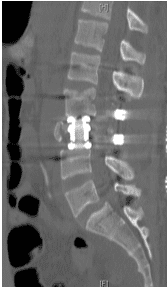

Patient was operated and the spinal canal cleaned up of all bony fragments. The spine was fixed from the side and the back to take care of instability.